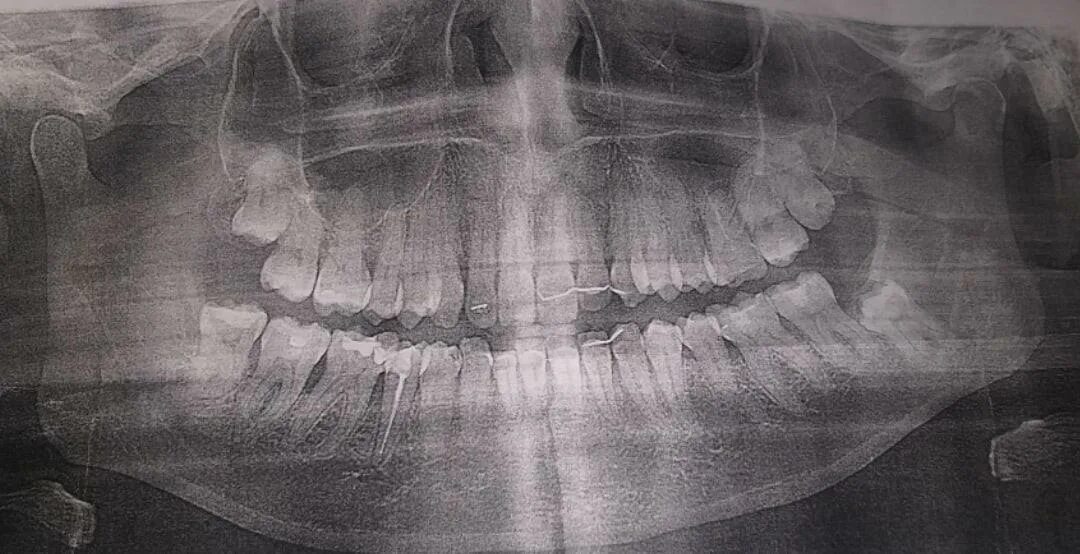

Как прочитать снимок